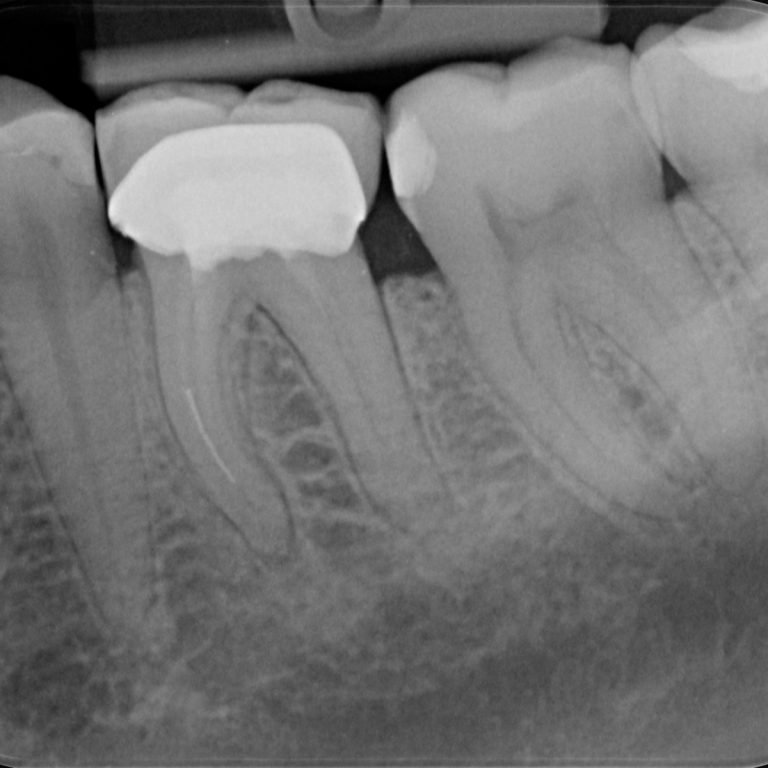

Root Canal Treatment

At Ashtead Dental, we understand that hearing "root canal" can feel daunting, but our expert dentists are here …